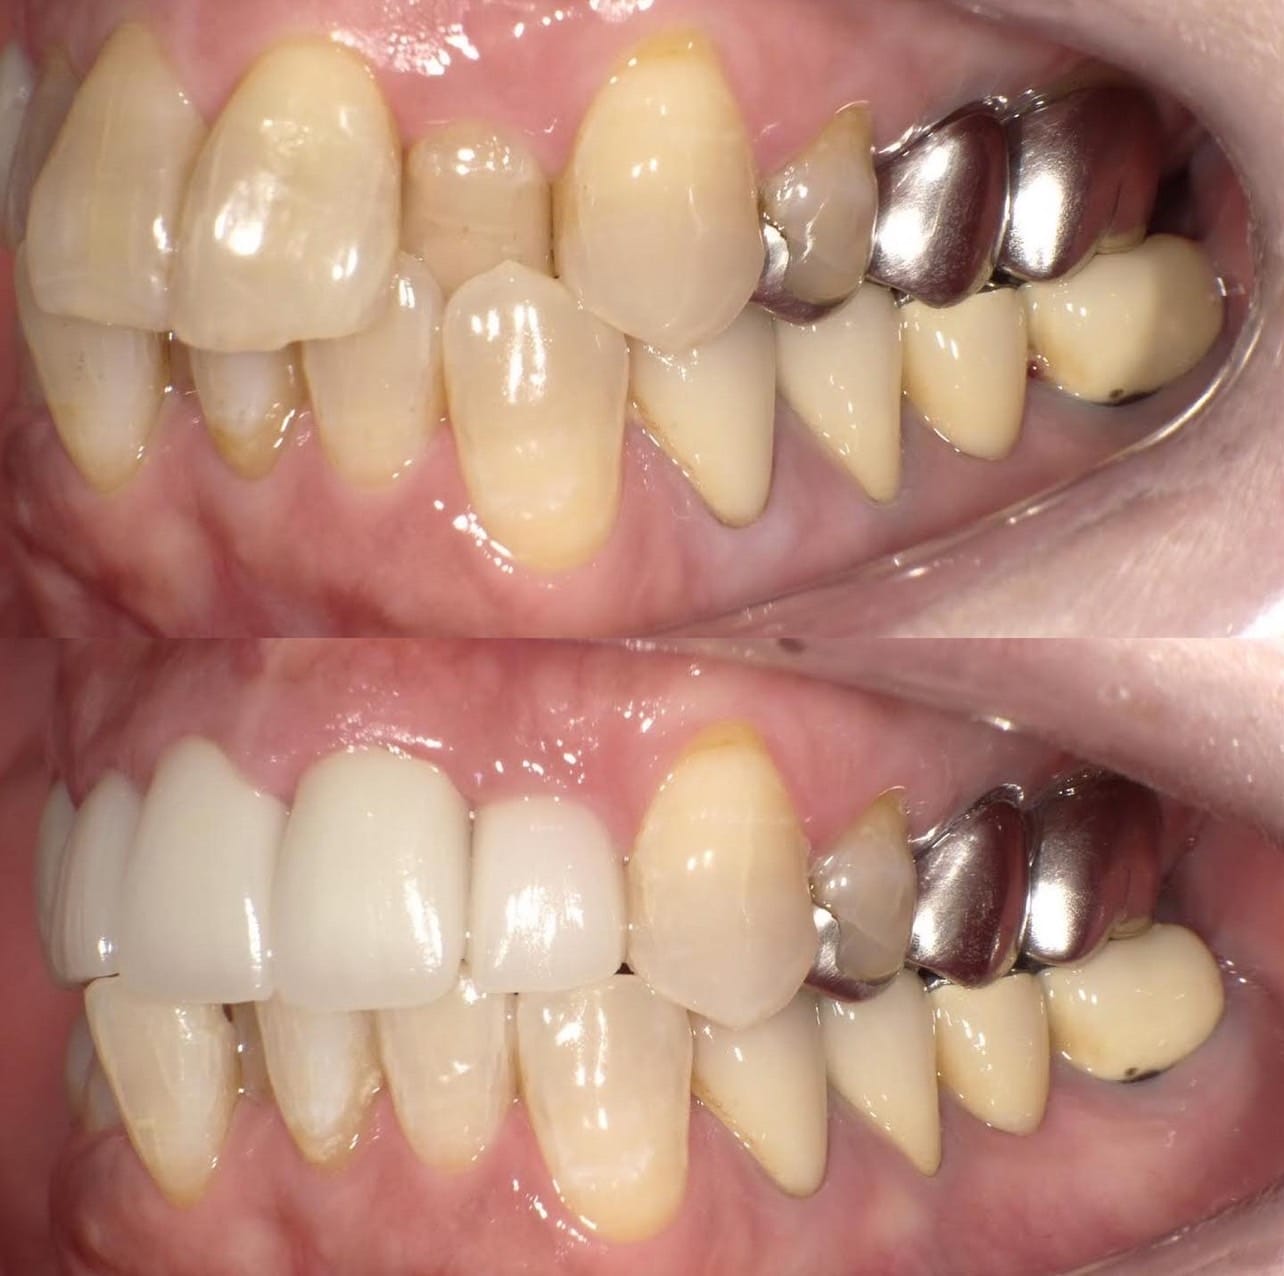

Case017 – インプラント

歯が欠けていて、隙間がある。

歯並びが気になる。

亀裂が入っている。

歯の無いところがある。

見える銀歯が気になる。

綺麗な口元になりたい。

という患者様の診療です。

上はジルコニアセラミックでかけているところを修復しながら、綺麗な歯並びで、患者様のお好きな白い歯に。

下の歯の無い所にはインプラント。

見える銀歯は外して綺麗な歯に修復。

また、ホワイトニングをして上の歯との色のギャップを少なくして、明るい口元にしました。